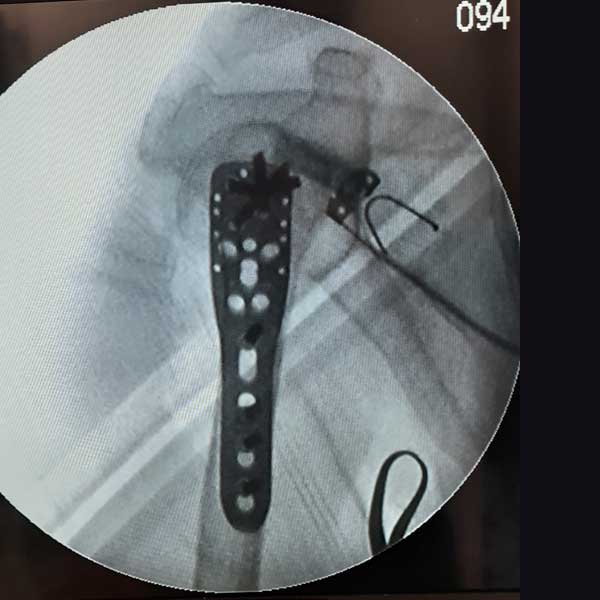

Case:14 Periprosthetic Fracture

60 years old patient with total knee replacement on left knee presented with open grade 1 injury. Debridement & slab given on emergency bases. Fixation with plate & screws done. Union was seen after 6 months.

Immdiate Post-op